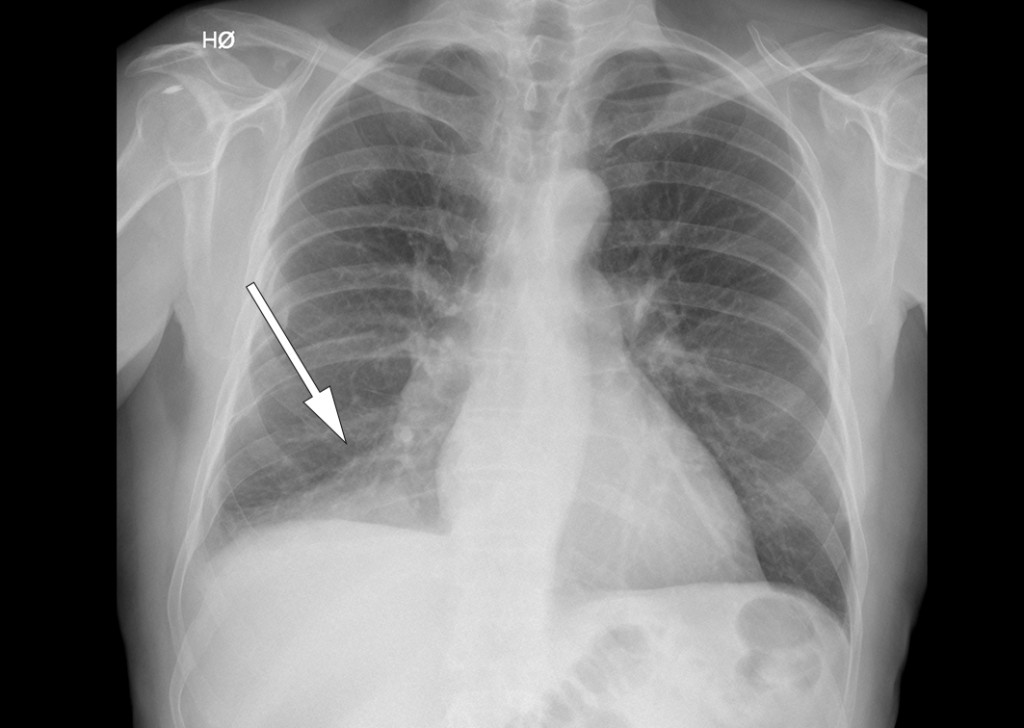

På grunn av klinisk mistanke om pneumoni ble det tatt røntgen thorax (se røntgenbildet) som viste en fortetning i høyre underlapp. Etter hvert kom det frem at pasienten flere uker tidligere hadde spist kjøttsuppe med grønnsaker, og at han under måltidet hadde registrert at «noe» forsvant ned i luftrøret.

Sykehistorien reiste nå spørsmål om fremmedlegeme, og pasienten ble innlagt i lungeavdelingen for behandling med penicillin intravenøst og videre utredning. Før bronkoskopi ble det utført CT thorax (se CT-bildet) som viste en 8 mm rund forandring proksimalt i høyre underlappsbronkus. Denne ga nær full okklusjon av lumen og forårsaket atelektase av høyre underlapp distalt.